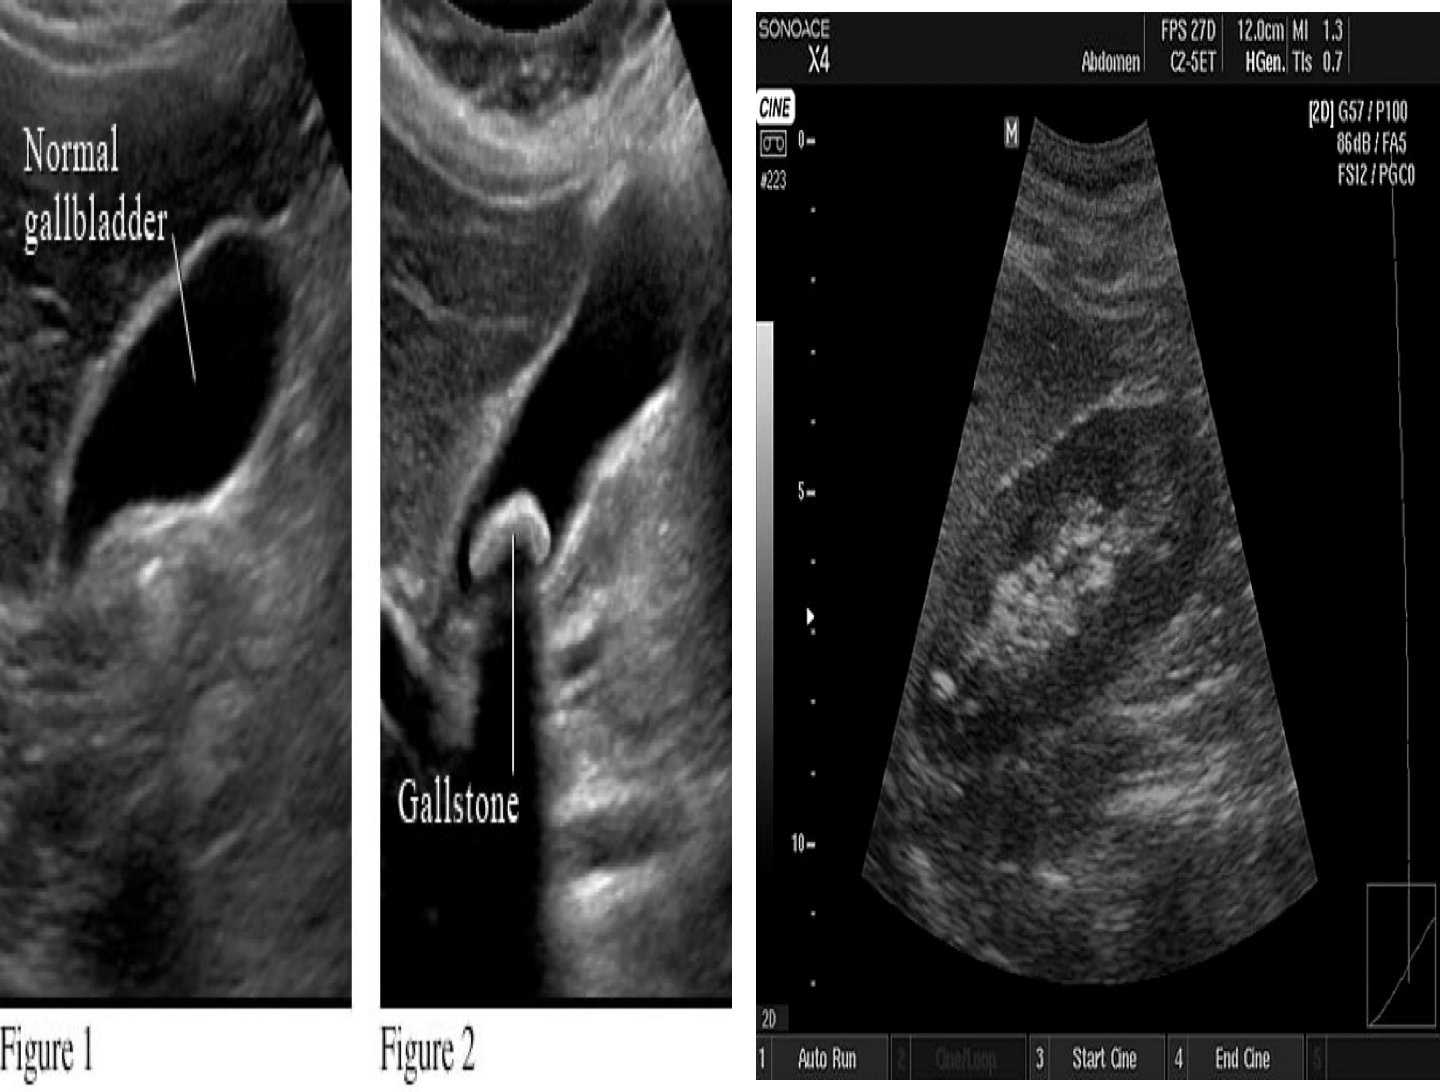

Acoustic shadow:

If ultrasound waves are strongly absorbed and echoed at the surface, the waves will fail to penetrate the tissue. All structures behind the surface will appear black. - Hypo-echoic shadow